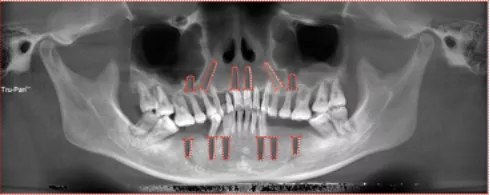

影像学检查

· 缺牙区骨量尚可,余留牙骨吸收至根尖1/3 。

· 双侧髁突骨皮质连续。

· 头影测量分析,临床诊断为:上颌前突,骨性二类错合畸形,上下中切牙及上下唇前突。

· 根据患者诉求、面型、剩余骨量、余留牙状况,拟拔除全部余留牙行全口种植固定修复。

· 上下颌计划各植入六颗straumann钛锆种植体行即刻种植即刻修复。